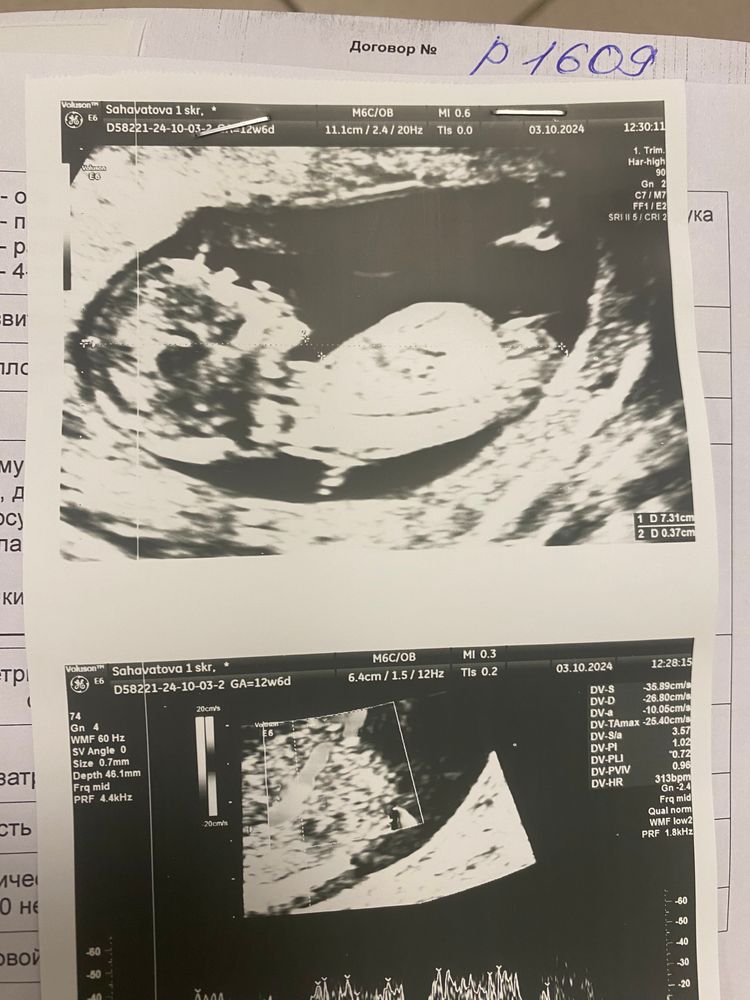

13 недель🍎. Первый скрининг🤰🏼🩷

Наши будни, наши неделькиСамое главное за эту неделю - я сходила на первый скрининг🥺

У нас все прекрасно, а это самое главное💗💗💗

На скрининг ходила в 9 роддом, сразу после забронировала себе врача на роды, может еще схожу на экскурсию, но скорее всего останусь именно здесь